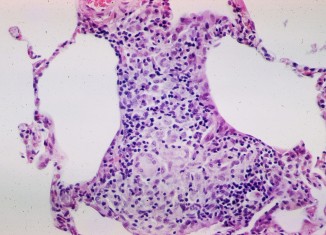

Sarcoidosis is a condition where small patches of inflamed cells show up in the body. The disease can affect parts of our body, including...

Before we go into the details of products that can be used for curing Lipoma, we should first know what the Lipoma is. Lipomas...